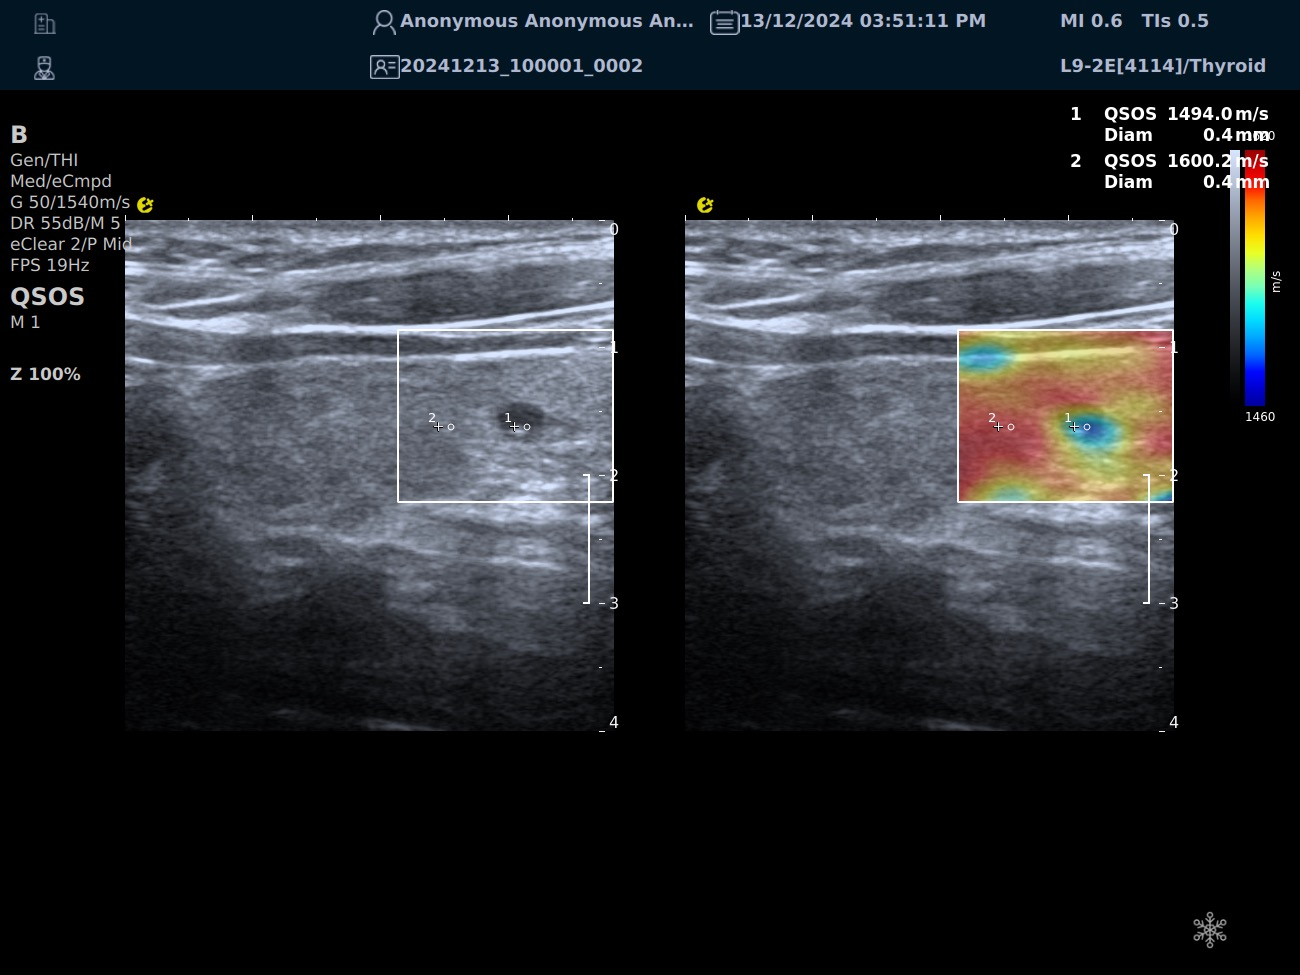

QSOS声速定量成像

测量原理

QSOS声速成像技术利用声波在组织中的传播速度差异性,计算不同位置的声速值,反映组织的物理特性。

成像过程

利用超声探头发射超声波脉冲,分析反射信号的时间延迟,确定声波传播路径和速度,构建声速分布图像。

图像显示

QSOS技术采用彩色编码显示声速图像,不同颜色代表不同声速值,便于医生识别病变部位和测量。

技术优势

?精准定量反映组织特性,成像更敏锐?彩色编码直观显示,轻松发现异常?捕捉声速差异,早期、微小病变更易察觉

肌骨领域的应用

?精准定位损伤部位?判断损伤严重程度?监测肌肉营养?评估肌少症?骨质疏松评估